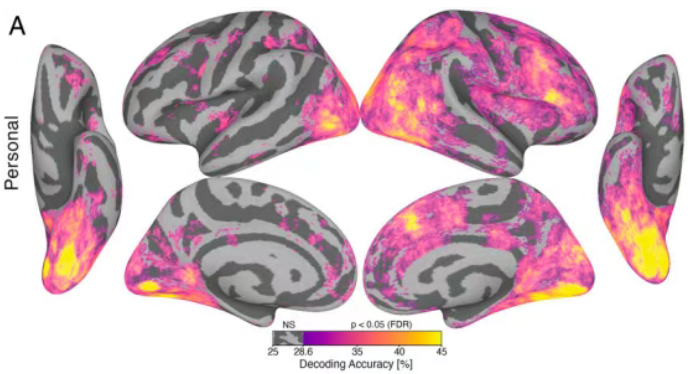

三、大脑激活:解读“思考现场”

人脑在执行特定任务(如看图片、做数学题、回忆事情)时,与该任务相关的脑区可能会被激活。 科学家们借助fMRI可获得人体大脑在这些任务状态下的图像数据,通过对比不同任务下的大脑激活图,就能知道哪些脑区参与了特定类型的思考或感知。比如,观看人脸时,与面孔识别相关的‘梭状回面孔区’可能会被激活。

大脑激活图

通过探测不同任务状态下大脑的血氧变化,磁共振技术得以标识忙碌的脑区。这为研究大脑工作机制,理解大脑的各种功能提供了强大工具。